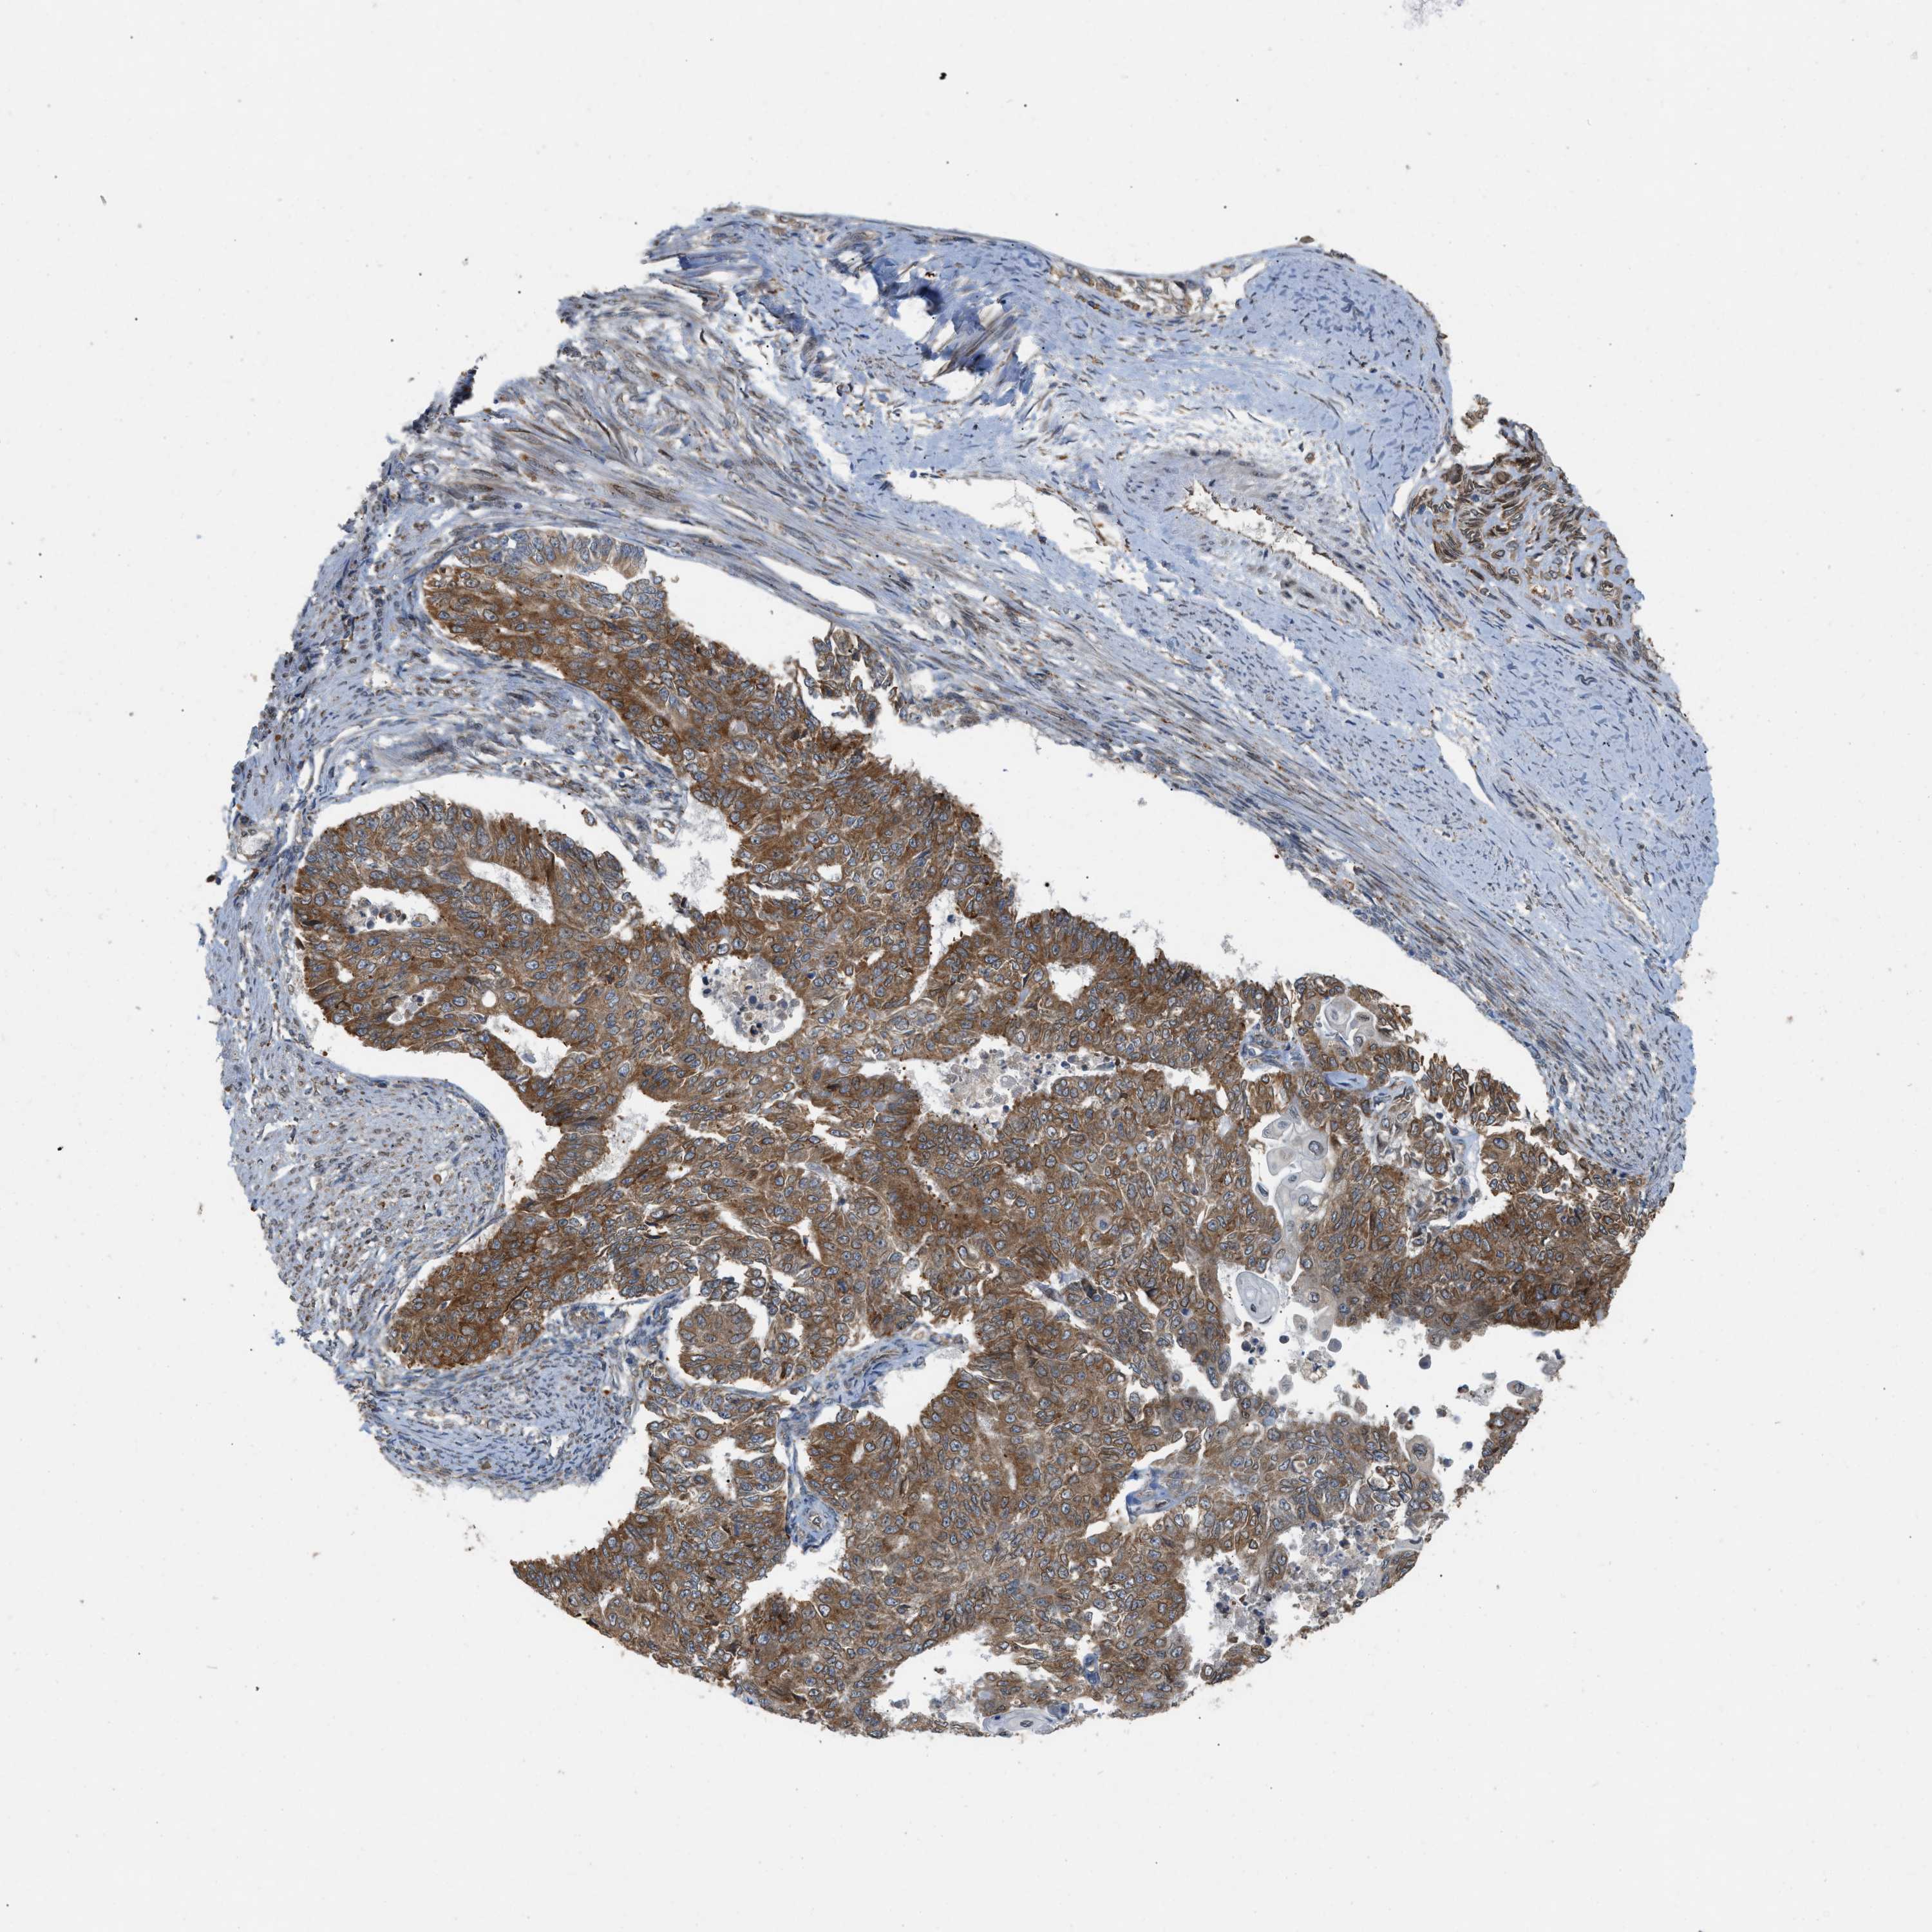

ENDOMETRIAL CANCER - Protein expressioni

A mouse-over function shows sample information and annotation data. Click on an image to view it in a full screen mode. Samples can be filtered based on level of antibody staining by selecting one or several of the following categories: high, medium, low and not detected. The assay and annotation is described here.

Note that samples used for immunohistochemistry by the Human Protein Atlas do not correspond to samples in the TCGA dataset.

Antibody stainingi

Antibody staining in the annotated cell types in the current human tissue is reported as not detected, low, medium, or high, based on conventional immunohistochemistry profiling in selected tissues. This score is based on the combination of the staining intensity and fraction of stained cells.

Each image is clickable and will lead to virtual microscopy that enables deeper exploration of all samples and also displays staining intensity scores, fraction scores and subcellular localization as well as patient and tissue information for each sample.

Antibody HPA014394

Staining

High

Medium

Low

Not detected

Intensity

Strong

Moderate

Weak

Negative

Quantity

>75%

75%-25%

<25%

None

Location

Nuclear

Cytoplasmic/membranous

Cytoplasmic/membranous,nuclear

Adenocarcinoma, NOS